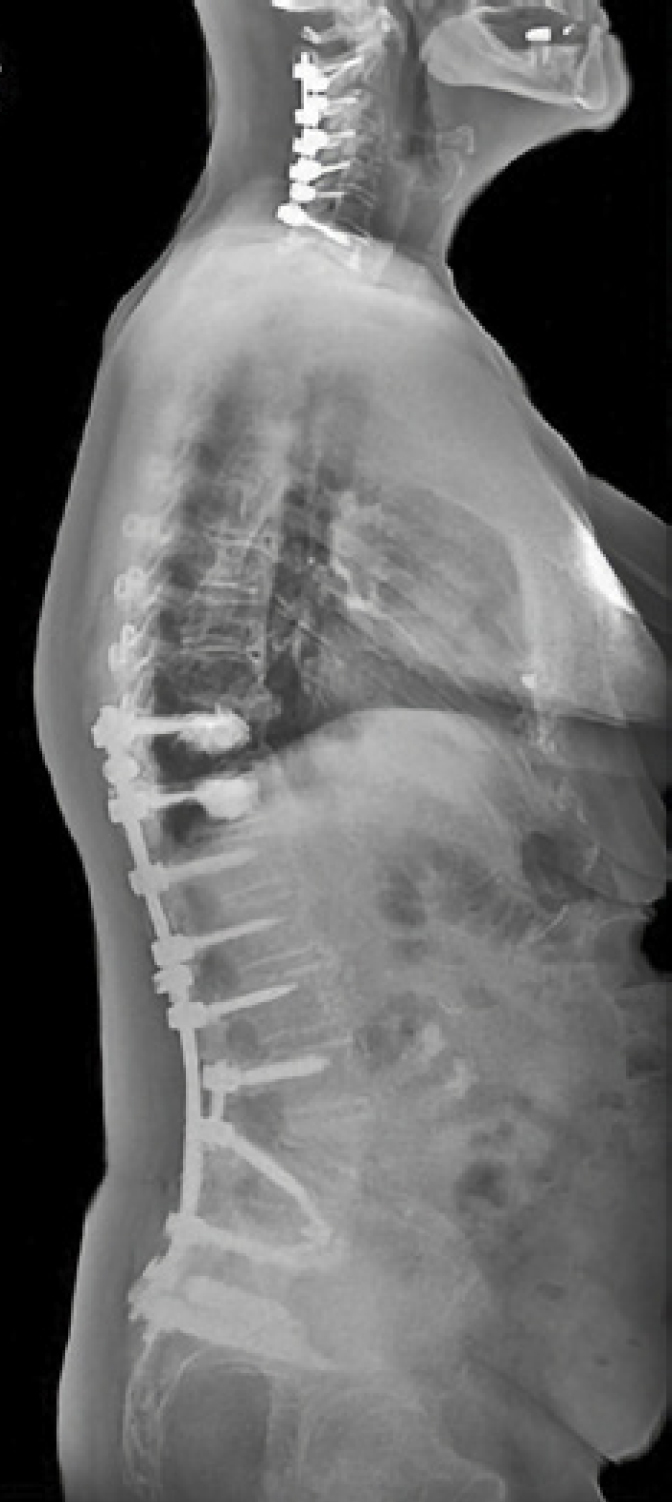

Fixed Sagittal Plane Deformity1

Patient History:

- 69 y/o female with history of multiple prior spine surgeries including L3-S1 fusion

- Presented with progressive pain and disability from sagittal plane deformity

- Symptomatic SI joint arthropathy likely accelerated by her prior lumbosacral fusion. 4/5 provocative maneuvers positive. Positive response to SI injection

- Failed to improve with exhaustive non-surgical management including PT and injections

Surgical Treatment:

- T10-pelvis posterior fixation and fusion

- L4 pedicle subtraction osteotomy (PSO)

- Bilateral placement of iFuse 3DTM implants using the Bedrock® technique

- Four points of SIJ fixation

Post-op:

- PI-LL: 43° to 7°, C7-SVA: 24cm to 5cm

- Back and SI joint pain improved post-operatively. Improvement persisted at 2 years.2